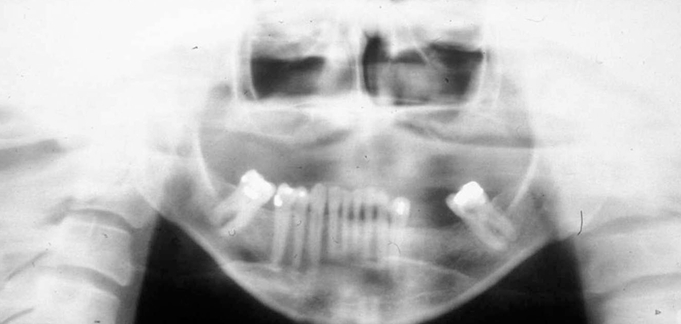

What is wrong with this image?

chin down